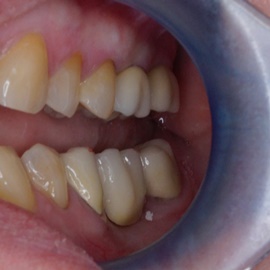

Implantacja natychmiastowa. Zęby paradontyczne. Usuniete zgodnie z popularną obecnie na zachodzie techniką: usuń zęby zanim zaniknie kość. Wynikiem takiego postępowania jest mniejsza trauma dla pacjenta i krótszy okres trwania rehabilitacji protetycznej, niższe całkowite koszty leczenia. Ale jednocześnie więcej implantów i mniej własnych zębów. W długotrwałym okresie obserwacji takie podejście daje dobre wyniki.